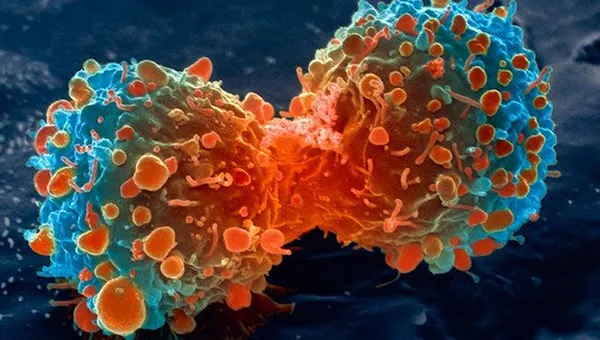

Phương pháp mới ngăn chặn tế bào ung thư phát triển

VTV.vn - Các nhà khoa học đã phát triển một loại thuốc mới có khả năng ngăn chặn sự phát triển của tế bào ung thư bằng cách làm tê liệt đồng hồ sinh học của chúng.

Theo nghiên cứu được công bố trên Tạp chí Science Advances, các nhà khoa học tại Trung tâm Sinh học hội tụ Michelson tại Đại học Nam California (USC) của Mỹ và Viện Phân tử sinh học biến đổi tại Đại học Nagoya của Nhật Bản đã đưa ra một hướng nghiên cứu mới - thay đổi các nhịp sinh học trong cơ thể để chống lại ung thư.

Các nhà khoa học đã tiến hành nghiên cứu tế bào ung thư trên thận người và bệnh bạch cầu tủy cấp tính ở chuột xuất phát từ giả thuyết ban đầu rằng việc đảo lộn giấc ngủ và các thành phần khác trong nhịp sinh học có thể gây hại cho sức khỏe con người, điều này cũng đúng với các tế bào. Nếu đồng hồ sinh học của các tế bào ung thư bị rối loạn, chúng có thể bị tổn thương hay thậm chí bị tiêu diệt.

Các nhà khoa học đã tìm ra một phân tử có tên GO289 có thể tác động lên enzyme khống chế nhịp sinh học của tế bào. Loại protein này sẽ phá vỡ chức năng của 4 loại protein khác vốn có vai trò quan trọng giúp tế bào ung thư sinh trưởng và tồn tại. Đặc biệt, GO289 làm chậm vòng tuần hoàn và gây lỗi nhịp sinh học của tế bào ung thư, mà lại ít ảnh hưởng đến các tế bào khỏe mạnh.

tế bào ung thư

tế bào ung thư